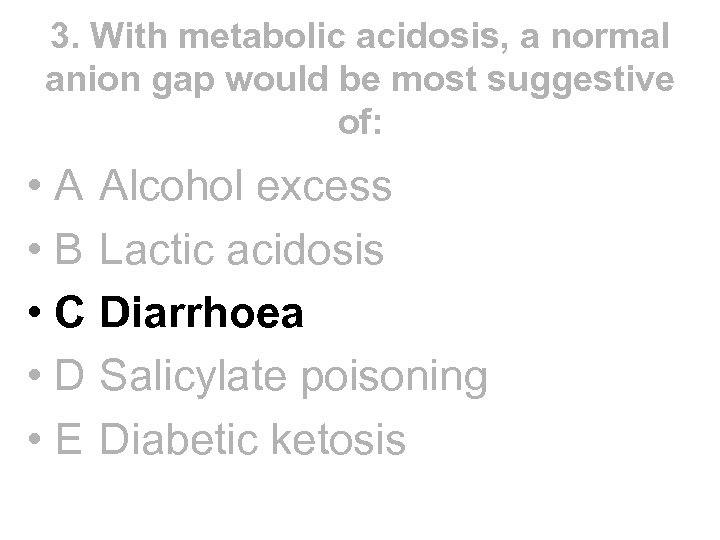

3. With metabolic acidosis, a normal anion gap would be most suggestive of: • A Alcohol excess • B Lactic acidosis • C Diarrhoea • D Salicylate poisoning • E Diabetic ketosis

3. With metabolic acidosis, a normal anion gap would be most suggestive of: • A Alcohol excess • B Lactic acidosis • C Diarrhoea • D Salicylate poisoning • E Diabetic ketosis

3. With metabolic acidosis, a normal anion gap would be most suggestive of: • A Alcohol excess • B Lactic acidosis • C Diarrhoea • D Salicylate poisoning • E Diabetic ketosis

3. With metabolic acidosis, a normal anion gap would be most suggestive of: • A Alcohol excess • B Lactic acidosis • C Diarrhoea • D Salicylate poisoning • E Diabetic ketosis